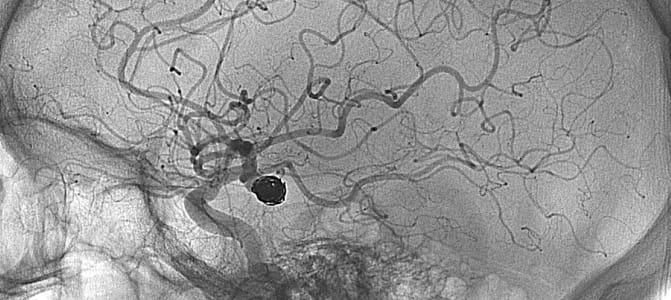

Stroke in brain image

Strokes caused by large blood clots in the brain are less likely to result in disability or death if the blockage is removed in the crucial early hours, according to reaffirming new research widely celebrated Wednesday.